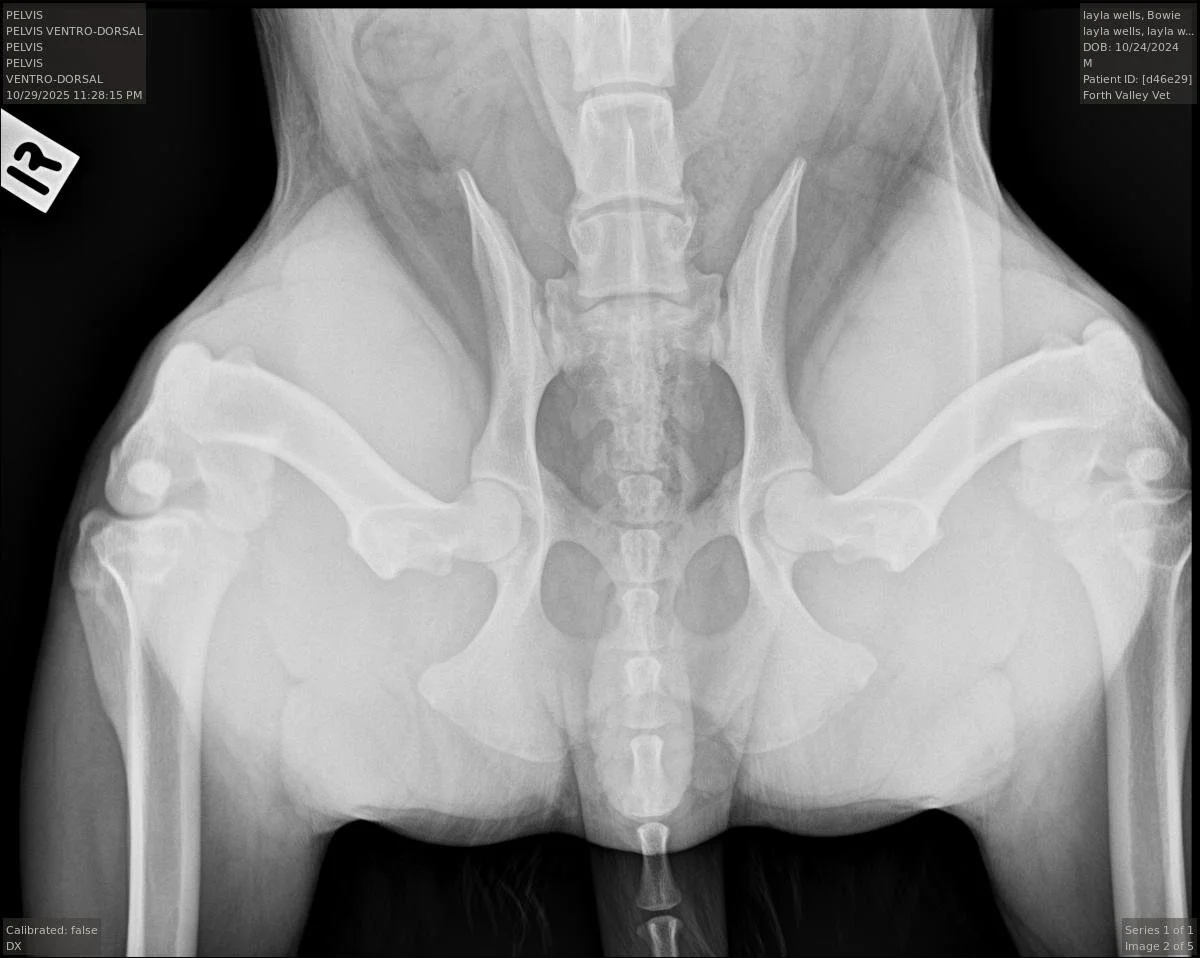

For decades, the industry standard was the "Hip-Extended View." While we still use this view to look for existing arthritis, it has a major flaw when it comes to prediction.

When a dog’s legs are pulled straight back for a traditional X-ray, the joint capsule twists and tightens up.

This can artificially force a loose hip into the socket, making it look "good" on film even if it is loose.

The Traditional Hip-Extended View: To check for any existing osteoarthritis.